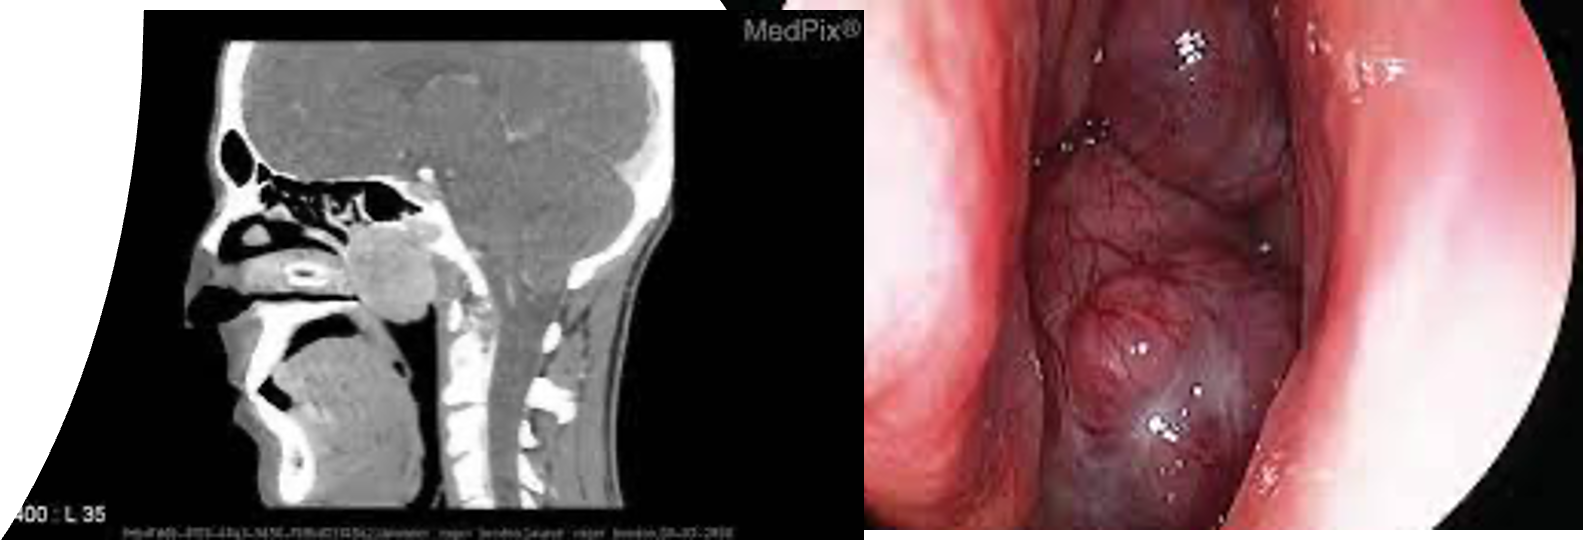

1. A smooth, lobulated, firm, easily bleeding mass:

• Seen in the nose.

• Depresses the palate and appears behind it.

• Imaging: CT and MRI